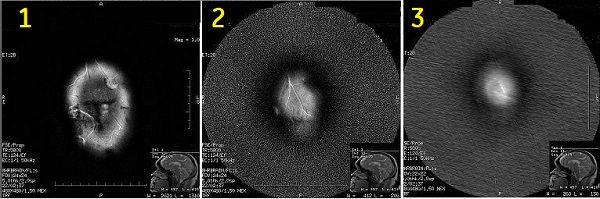

Blurred images

Blurred images can be seen with all three PROPELLER applications and results from a failure to match enough blades. If the acquired blades correlate poorly with each other, the following message appears in the GE syslog:

“Image quality may be degraded due to poor blade correlation…".

Signal voids

Signal voids can appear in diffusion weighted images produced by DW PROPELLER and are often indicated by black holes, but it may not occur with every scan.

Signal voids may be caused by system calibrations out of spec (e.g., eddy currents).

Contact service to ensure the system is within specification.